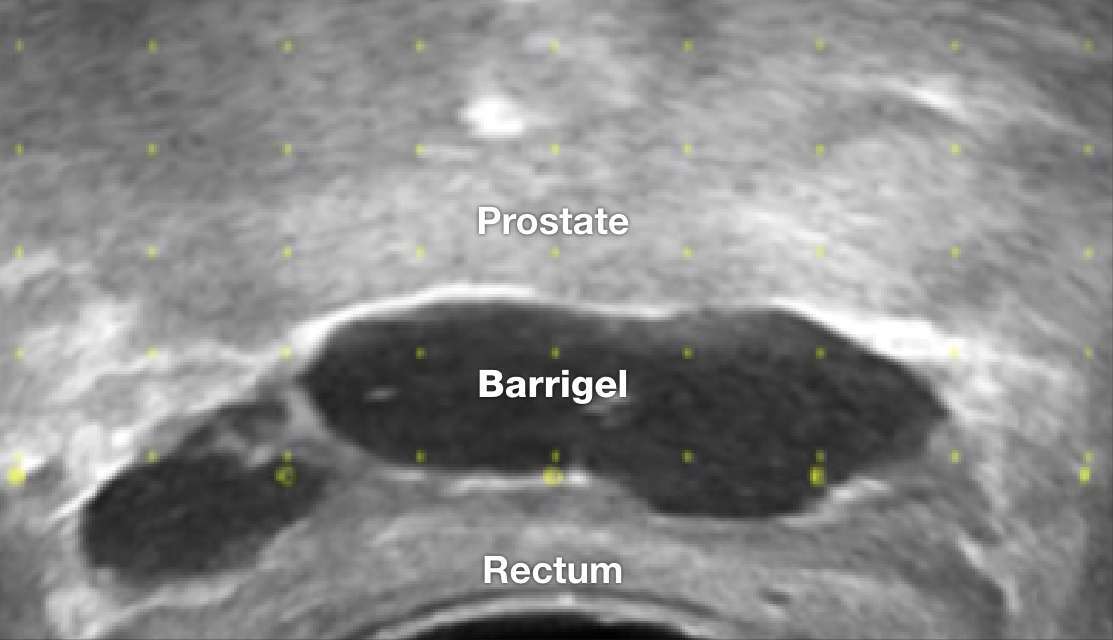

TRUS IMAGES

TRUS image courtesy of Prof Michael Chao, MBBS (Hons), FRANZCR, AFRACMA, DMedSc, Radiation Oncologist; Victoria, Australia